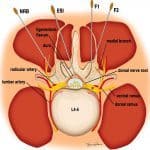

Đau cột sống là bệnh lý rất thường gặp. Nguyên nhân thường gặp nhất là thoái hóa đĩa đệm, cột sống. Trong số bệnh nhân có triệu chứng, rất ít trường hợp phải mổ, số còn lại cần được điều trị phục hồi chức năng, châm cứu, tiêm giảm đau… Tiêm giảm đau là phương pháp giảm triệu chứng nhanh nhất, hỗ trợ đắc lực cho các phương pháp điều trị khác, hạn chế tối đa các tai biến…